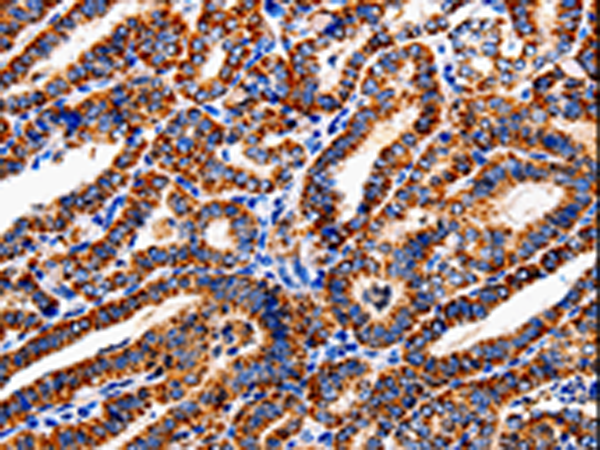

分类: 科研抗体货号: P00099别名: SR; BCSG1应用: WB,IHC反应种属: Human